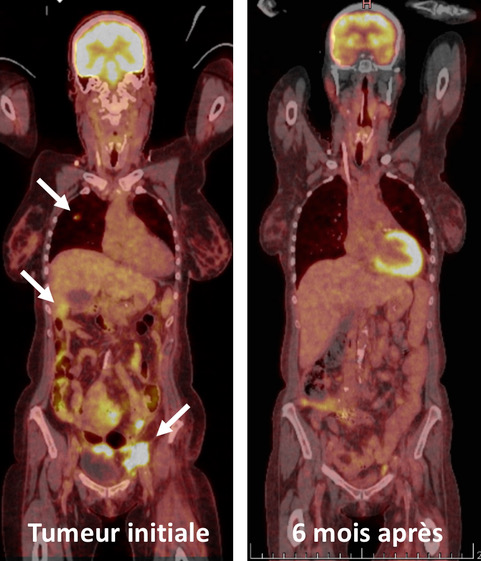

PET-CT-scanner montrant la tumeur du rein avec les métastases hépatiques et pulmonaires (gauche, flèches). PET-CT-scanner après la disparition complète des tumeurs à 6 mois (droite). © UNIGE

La lutte contre le cancer ne se solde pas toujours par une victoire. Aujourd’hui, les principaux traitements sont l’ablation chirurgicale de la tumeur, la chimiothérapie, la radiothérapie et, dans une moindre mesure, la stimulation du système immunitaire. Une équipe de l’Université de Genève (UNIGE) et des Hôpitaux universitaires de Genève (HUG) a traité une personne diabétique ayant développé une tumeur sur un rein qui lui avait été greffé neuf ans auparavant. Le cancer, très agressif, lui laissait statistiquement cinq mois d’espérance de vie. Rareté de ce cas: la tumeur provenait du rein du donneur et non de la patiente elle-même. Cette particularité a permis aux scientifiques d’attaquer la tumeur via un renforcement choc de son système immunitaire, ce qui lui a sauvé la vie. Aujourd’hui, sept ans après, cette femme se porte bien et n’a plus développé de cancer. Les résultats de cette étude, à lire dans la revue Transplantation, démontrent l’importance du développement de l’immunothérapie.